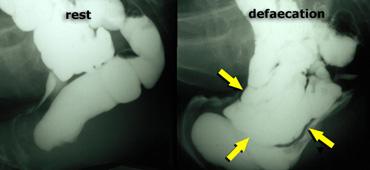

Cần chụp thêm các tư thế chếch hoặc thẳng trước-sau (AP) đối với bất kỳ hình ảnh X-quang nào chưa được giải thích rõ trên tư thế chiếu nghiêng bên (hình minh họa).

Trực tràng hình chữ S có thể giả lồng ruột trên tư thế chiếu nghiêng bên.

Bên trái là tư thế chiếu nghiêng bên và tư thế AP của một bệnh nhân có hình ảnh lồng ruột trên cả hai tư thế chiếu.

Bên trái là tư thế chiếu nghiêng bên và tư thế AP của một bệnh nhân có trực tràng hình chữ S, giả lồng ruột trên tư thế chiếu nghiêng bên.